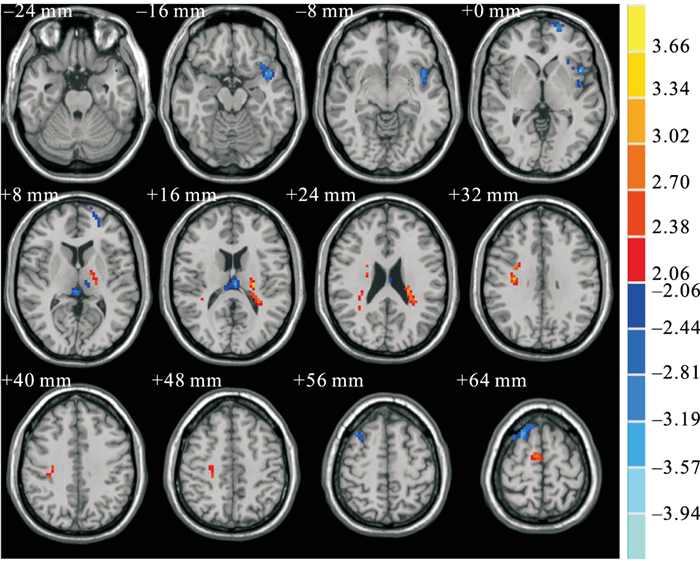

高危SUDEP組與低危SUDEP組間的ALFF值存在顯著差異,與低危患者相比,高危SUDEP組患者的ALFF值在右側背外側額上回、左側眶部額上回、左側島葉及左側丘腦的部分區域降低;而在右側內側和旁扣帶回、右側補充運動區及左側丘腦的部分區域增高(表 3, 圖 1)。

圖中暖色系代表ALFF值升高,冷色系代表ALFF值降低,閾值設定為

Warmer colours represents elevated ALFF values, and cooler colours represents decreased ALFF values. The statistical threshold was